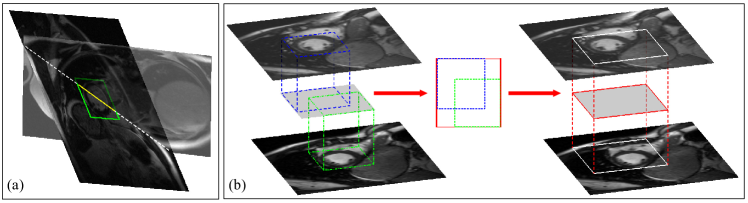

The discontinuity is measured by the dissimilarity between two regions of the same area sampled from adjacent SA slices. Although the LV appears different in adjacent slices due to different imaging locations, the change is gradual. Therefore, by minimizing the dissimilarity via translation of slices, the original relative positions of the SA slices can be recovered. Again the ROI is predefined for each SA slice. However, since the ROI is defined as the bounding box which well contains the LV, its size is varied for most SA slices as the LV size varies in most SA slices; furthermore, during the translation, SA slices are deviated from each other, and so are their ROIs. To solve this problem, we project the two ROIs of adjacent SA slices onto a middle plane and find the smallest rectangle which can completely contain the two projections on that plane, and then project this rectangle back onto the SA slices under consideration to determine the regions used for the discontinuity measure (Fig. 3(b)). Noting that the projections are all along the normal to the SA planes, these procedures are actually finding the smallest cuboid whose top and bottom faces are in the SA slices (planes) under consideration and can completely contain the corresponding ROI in each slice. Denoting the two regions sampled from the two adjacent SA slices by and , the contiguous cost is defined as:

| (2) |

where denotes the adjacency of two consecutive SA slices, and is a function measuring dissimilarity between two regions. is also a function of IPP, as the regions sampled on adjacent SA slices are determined by their IPPs (plus the constants IOP and PS). Furthermore, because the translation of slices takes place in the patient coordinate system (instead of any of those coinciding with the SA plane), is fully dependent on slices’ translations in all -, -, and - directions.